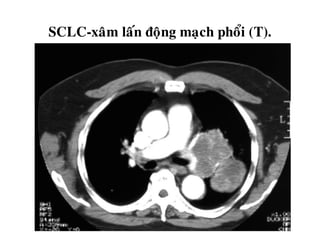

SCLC-xaâm laán ñoäng maïch phoåi (T).